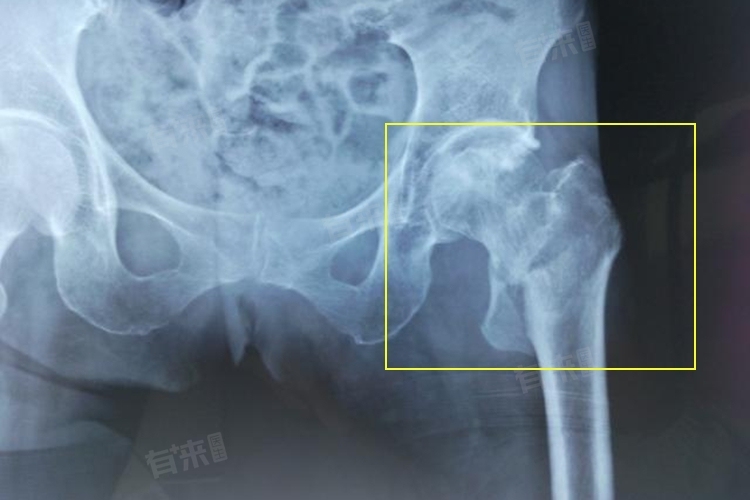

左股骨粗隆间骨折指发生在左侧股骨大小粗隆间区域的骨折,此部位血运丰富,但结构复杂,骨折后常出现髋部疼痛、肿胀、活动受限等症状。多因外力作用引发,严重影响患者肢体活动,需及时治疗,以促进康复、减少并发症。